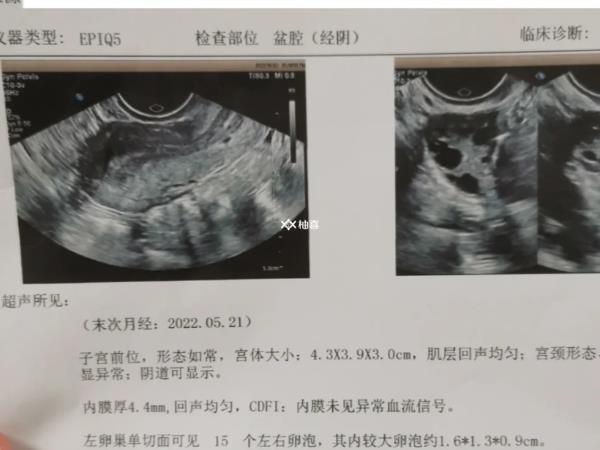

患者打促排卵针后长了12个卵泡,无其它异常情况下,可能是正常现象,毕竟有的患者本身基础卵泡较多,且对促排针药物反应较好,那么可以促使卵巢内的卵泡生长发育成熟,对此建议患者在此期间多注意观察卵泡发育情况及身体症状表现即可,无需过于担心。

打促排卵针后,B超检查发现长了12个卵泡可能会对身体产生一些影响,尤其是对于多囊卵巢综合征患者来说,可能会引起卵巢过度刺激综合征(OHSS),这是促排卵治疗中最常见的并发症之一,具体表现为腹痛、腹胀、恶心、呕吐等症状,严重还可能导致胸腔或腹腔积液等危险情况。